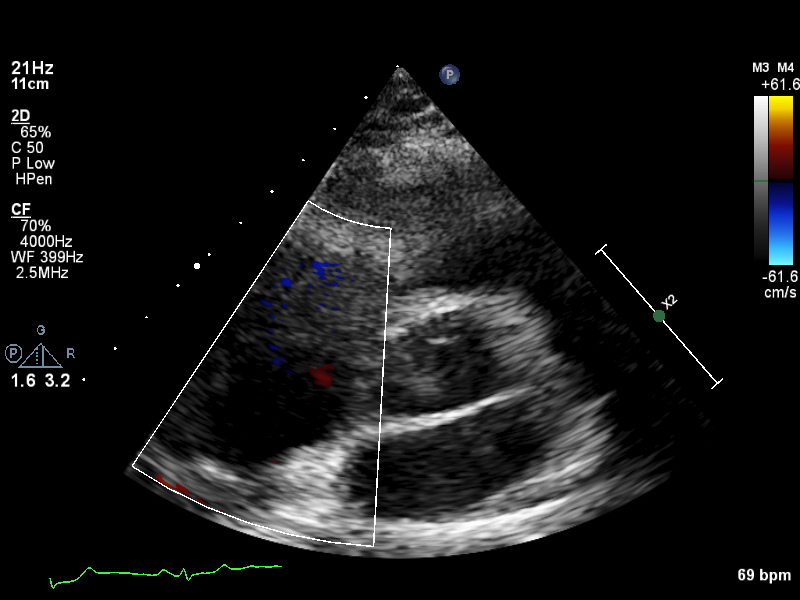

ImageView NameDescription

a4ch-ias a4ch-ias Apical 4-chamber, focused on the inter-atrial septum

a4ch-la a4ch-la A4CH with Doppler near MV/LA or 2D covering full LA, not full LV

a4ch-lv a4ch-lv A4CH covering the whole depth of the LV, not the whole depth of the LA

a4ch-ra a4ch-ra Apical 4-chamber focused on the right atrium, or colour Doppler on TV/RA

a4ch-rv a4ch-rv Apical 4-chamber focused on the right ventricle